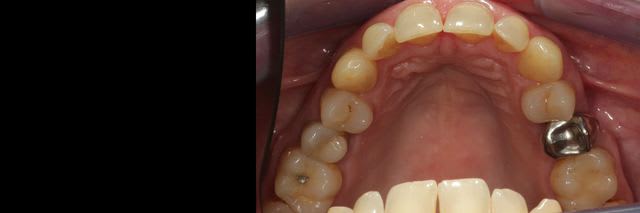

Cette patiente vient me voir pour trouver une solution pour sa 15, que proposez vous?

la dent a eu une résection apicale à l'ancienne il y a quelques années, est mobile, plus d'os en vestibulaire : No way!